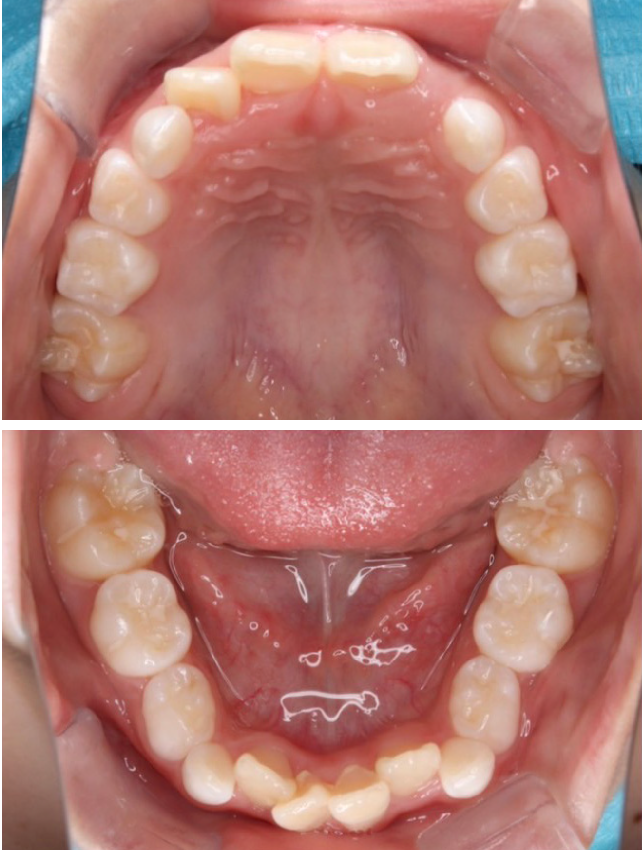

1期治療で使用する装置

拡大床

- 機能

- 横に広げるための装置

- 期間

- 6か月~10か月程度

成長期のお子さまの顎をゆっくりと広げる矯正装置です。顎の成長を正しい方向へ導くことで、歯がきれいに並ぶための土台を整えます。歯を無理に動かすのではなく、顎の成長を活かした治療のため、痛みが少なく、お子さまへの負担が比較的軽いのが特徴です。

拡大床は、多くの場合1期治療の中心となる装置で、将来的な本格矯正の必要性を減らすことにもつながります。 -

当院の症例

CASE